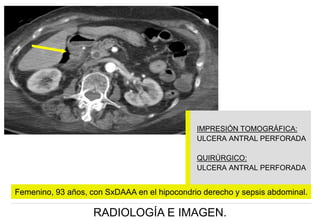

Femenino, 93 años, con SxDAAA en el hipocondrio derecho y sepsis abdominal. Cortes axiales

en fase arterial , identificando aire libre en la fosa vesicular y solución de continuidad de la región

antral.

IMPRESIÓN TOMOGRÁFICA:

ULCERA ANTRAL PERFORADA

QUIRÚRGICO:

Femenino, 93 años, con SxDAAA en el hipocondrio derecho y sepsis abdominal.